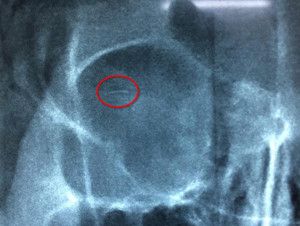

Những tưởng sẽ trở nên đẹp hơn khi tiêm filler nâng mũi, nhưng thiếu nữ 20 tuổi lại phải nhập viện cấp cứu vì mù mắt…